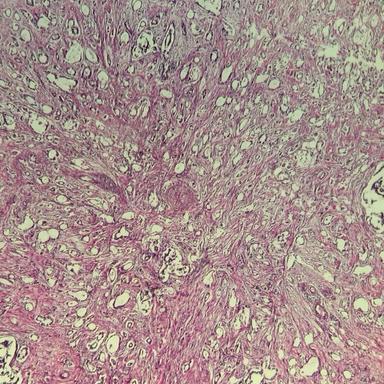

Invasive Ductal Carcinoma (IDC) Dataset

Our first prepared dataset is related to breast cancer, Invasive Ductal Carcinoma (IDC). This dataset has been collected from pathological biopsy samples of 150 patients (Grade I, II and III) who were referred to Anahid Clinic and Pour Sina Hakim Digestive Diseases Research Center, Isfahan University of Medical Science, during 2014-2019.

Each pathological sample in the dataset has four levels of magnification: 4x, 10x, 20x and 40x.

Magnification Samples

5x Magnification

10x Magnification

20x Magnification

40x Magnification